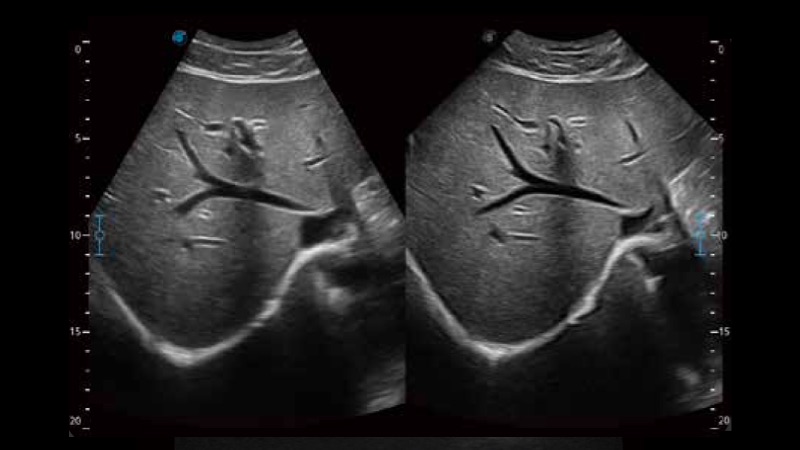

凭借开立医疗先进的成像技术和优异的探头技术提供的清晰的图像表现,您可以更自信地做出临床决策。